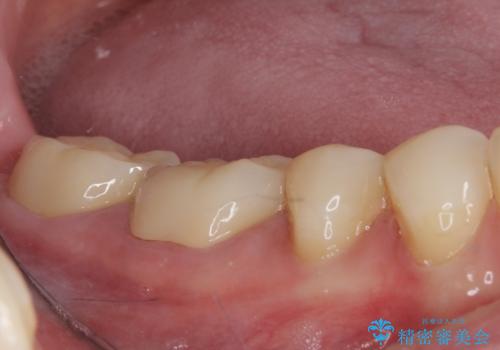

- 以前、職場近くで夜遅くまで治療していた医院で装着した奥歯のクラウンが、壊れたり汚れたりしていることを気にして来院された患者様です。

以前は安価であったことからハイブリッドクラウンを選択されたそうですが、すぐに具合が悪くなってしまったので、今回はオールセラミッククラウンにて補綴治療を行うこととしました。